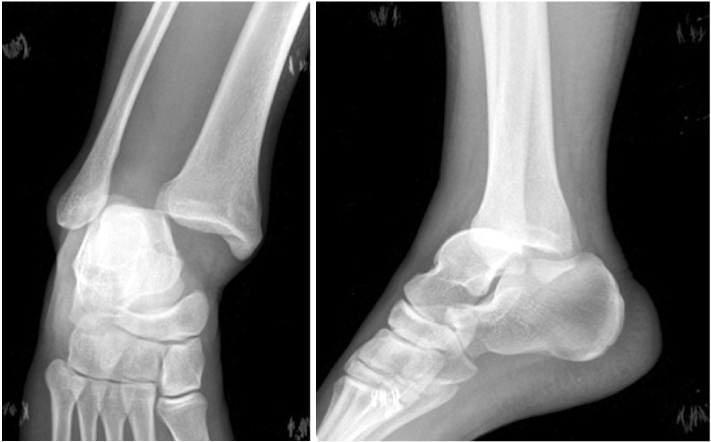

Fig. 2

(A) Anteroposterior view of right ankle shows widening of tibiofibular space and medial clear space.

(B) Lateral view shows equinus and flexion deformity of great toe.